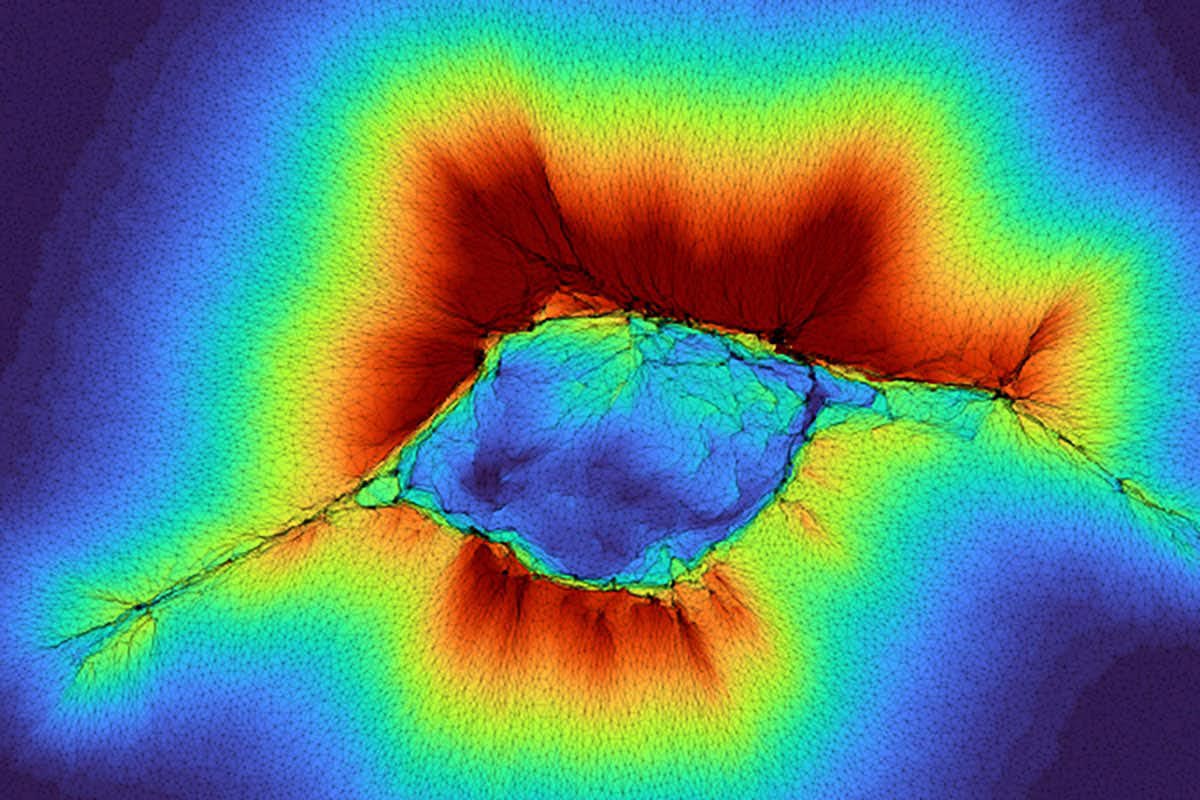

Amit Pathak, professor of mechanical engineering and materials science at the McKelvey School of Engineering, described this process as "depth mechano-sensing"—the ability of cells to perceive structures beneath the surfaces they adhere to. In earlier research, Pathak and his team discovered that abnormal cells with "high front-rear polarity" (a feature typical of cells in motion) can detect their surroundings up to 10 microns beyond the layer they are attached to.

This extended sensing occurs as the cell reshapes the surrounding fibrous collagen, allowing it to probe deeper into the extracellular matrix (ECM) and "feel" what lies ahead—whether a dense tumor, soft tissue, or bone. A single abnormal cell can gauge the stiffness of the ECM and navigate based on this mechanical feedback.

The new research shows that a collective of epithelial cells, found on the surface of tissue, can do the same and then some, working together to muster enough force to "feel" through the fibrous collagen the layer as far as 100 microns away.

"Because it's a collective of cells, they are generating higher forces," said Pathak, who authored the research along with PhD student Hongsheng Yu.

According to their models, this occurs in two distinct phases of cell clustering and migration. What those clustering cells "feel" will impact migration and dispersal.